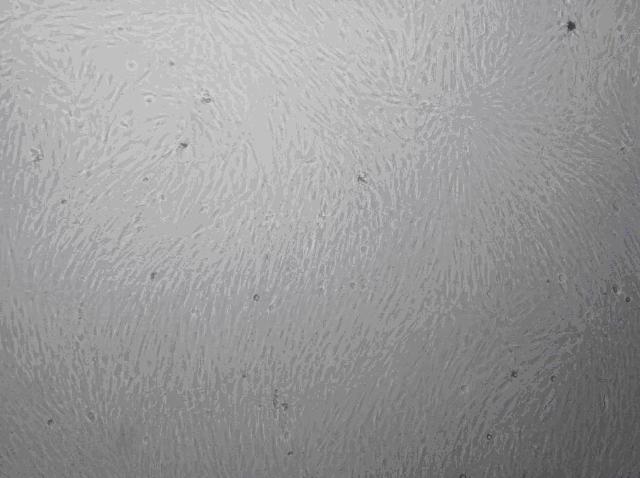

公司與浙江大學培育出小鼠骨髓間充質干細胞

名稱:小鼠骨髓間充質干細胞(Mouse Msenchymal Stem CellmMSC

產地:杭州大力神醫療器械有限公司和浙江大學細胞與遺傳學研究所

細胞來源:取自小鼠骨髓,傳代培養至第三代,每瓶細胞長滿可達8×105-1×106個細胞。

細胞特性:流式檢測結果顯示,CD34CD45陰性,CD44CD29CD166陽性。

培養和誘導分化結果顯示,本產品具有良好的增殖和分化潛能,可分化為成骨細胞、脂肪細胞、軟骨細胞、神經細胞等。

質量控制:本產品無細菌、真菌、霉菌、病毒、支原體污染。

運輸保存:本產品為新鮮培養細胞,室溫下保存運輸。

細胞培養:采用α-MEM培養液(貨號GNM11900-S)培養,添加10%四季青無支原體胎牛血清。當細胞生長至80-90%融合時利用0.25%Trypsin 0.02%EDTA(貨號GNM25200)消化,傳代培養。切勿使細胞長的太滿,否則會有接觸抑制效應,且會影響細胞的增殖和分化能力。

產品承諾:小鼠骨髓間充質干細胞的體外培養周期有限。建議使用配套的培養基和正確的培養方法來培養、傳代,以此保證細胞具備良好的增殖和分化能力。

產品用途:本產品只提供給進一步的科研使用,不可應用于治療等其他方面。